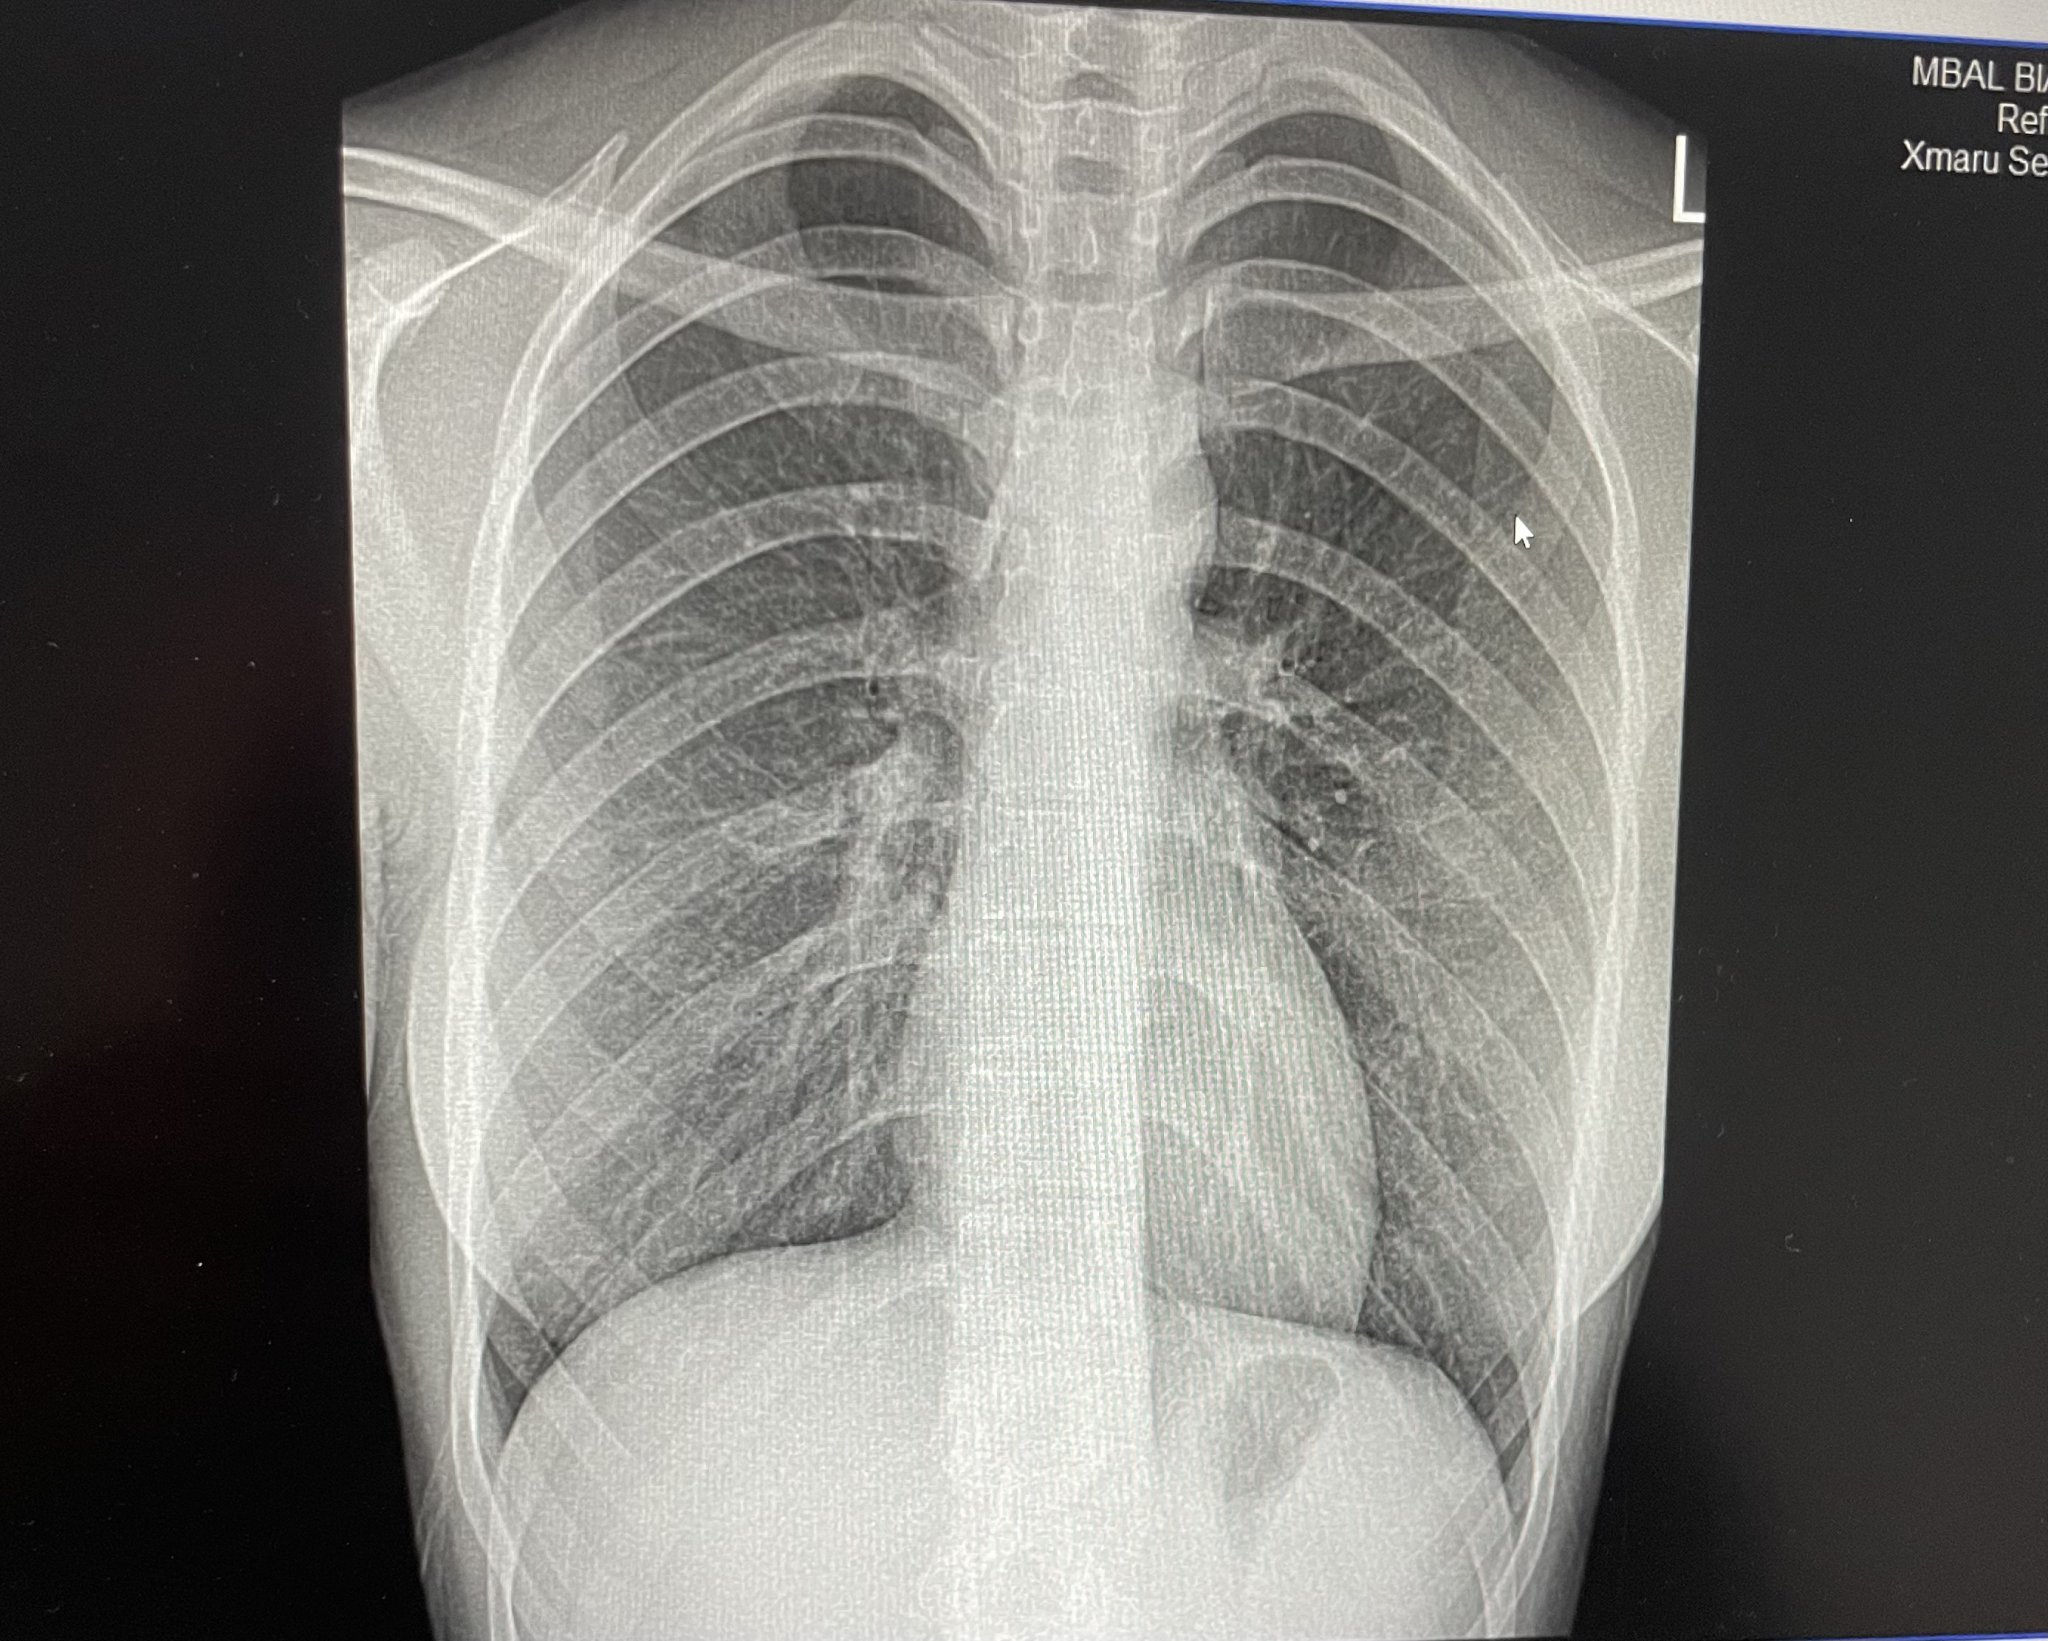

Здравейте, много ви моля без нападки и подобни неща. Достатъчно съм уплашена. На 16.05.24 ми правиха рентгенография на гръден кош и бял дроб, отидох на лекар с оплакванията: нямам достатъчно въздух, задъхвам се при всяко движение. Изпратиха ме на снимка, отидох, но няма кой да я разчете, казаха ми чак в понеделник, но не мога да чакам до тогава, не знам какво да правя, страх ме е.. моля ако някой разбира да си каже мнението.

Нищо не разбирам но на мене ми изглежда добре. По принцип се гледа да е хомогенна снимката. Да няма сенки. Не се притеснявай. Не се вижда много добре. Няма ли някаква констатация на ретгенолога?

https://,не съм доктор,но съм изяла доста рентгенови снимки в живота си . Снимката е чиста ,ако се притесняваш че има нещо страшно .По вероятно да става дума за задушаване от алергия,която се проявява лятото от разцъфтяването на дърветата,цветя .

Включително и паник атаки,но снимката е Ок

Диагнозата е бронхит - усилен белодробен рисунък има.